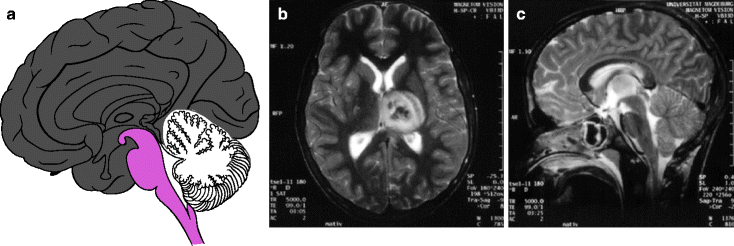

Parkinsonsyndrome Fallstricke Bei Der Diagnose